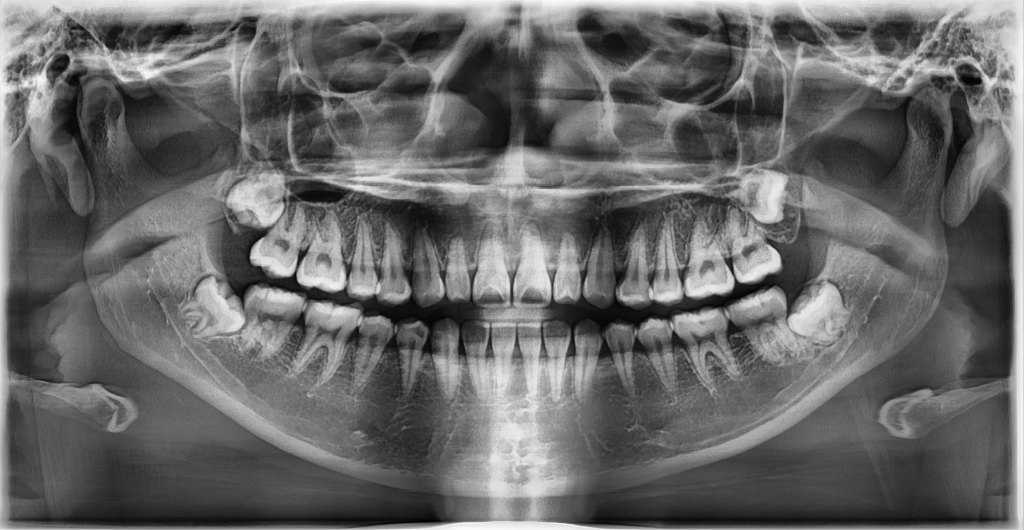

의사 분 말씀을 들어 보니 사랑니를 발치할 생각이 아니면 ct를 찍을 필요는 없다고 하시더라고요. 그래서 아래에 첨부한 파노라마만 보고 이야기를 나누었는데...

의사 선생님 말씀으로는 위쪽 사랑니 두 개는 평생 문제 일으킬 일 없고, 아래쪽 사랑니 두 개도 웬만하면 문제 없을 거라고 하시더라고요. 또 사랑니들이 너무 깊숙이 있다고... 그래서 굳이 지금 발치할 필요는 없다고 하시기에 그날은 스케일링만 받고 나왔거든요.

1. 엑스레이 상으로 볼 때 제 사랑니가 신경을 누르고 있거나, 나중에라도 신경을 누를 확률이 큰가요? 뽑아야 하는 사랑니인가요?

2. 우선은 경과를 지켜보면서 6개월~1년 주기로 엑스레이를 찍으며 사랑니의 상태를 확인해 볼까 하는데, 그러지 말고 다른 치과에 가서 ct를 찍어 더 정밀하게 확인하거나, 아니면 차라리 미리 발치를 해서 혹시 모를 문제를 방지하는 게 좋을까요?